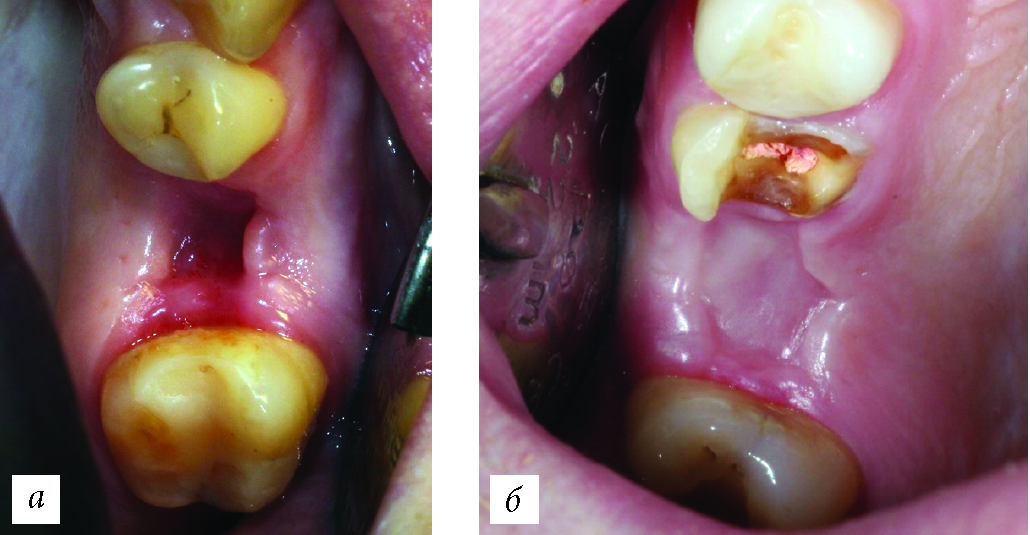

В контрольную группу исследования были включены 18 пациентов, которым было проведено 20 хирургических вмешательств, заживление костного дефекта во всех клинических случаях проходило под кровяным сгустком (рис. 1). Всего было проведено 12 операций удаления зубов, 5 операций удаления ретенированных зубов, 3 операции цистэктомии с резекцией верхушки корня. Необходимо отметить, что во всех группах отдельно выделялась только полная ретенция зуба (без нарушения целостности слизистой), неполную ретенцию, согласно распределению, относили в графу «Удаление зуба».

Рис. 1. Выполненные оперативные вмешательства в контрольной группе (заживление под кровяным сгустком).

В 1-й группе исследования выполнено 26 хирургических вмешательств, все костные дефекты после операции заполнялись крошкой коллагенового биоматериала. У 20 пациентов выполнено 16 удалений зубов, 4 удаления ретенированных зубов, 6 цистэктомий с резекцией верхушки корня (рис. 2). Перед применением материал смешивался в течение 10 мин. с физиологическим раствором до приобретения им желеобразной формы.

Рис. 2. Выполненные оперативные вмешательства в первой группе исследования (коллагеновый материал в виде порошка).